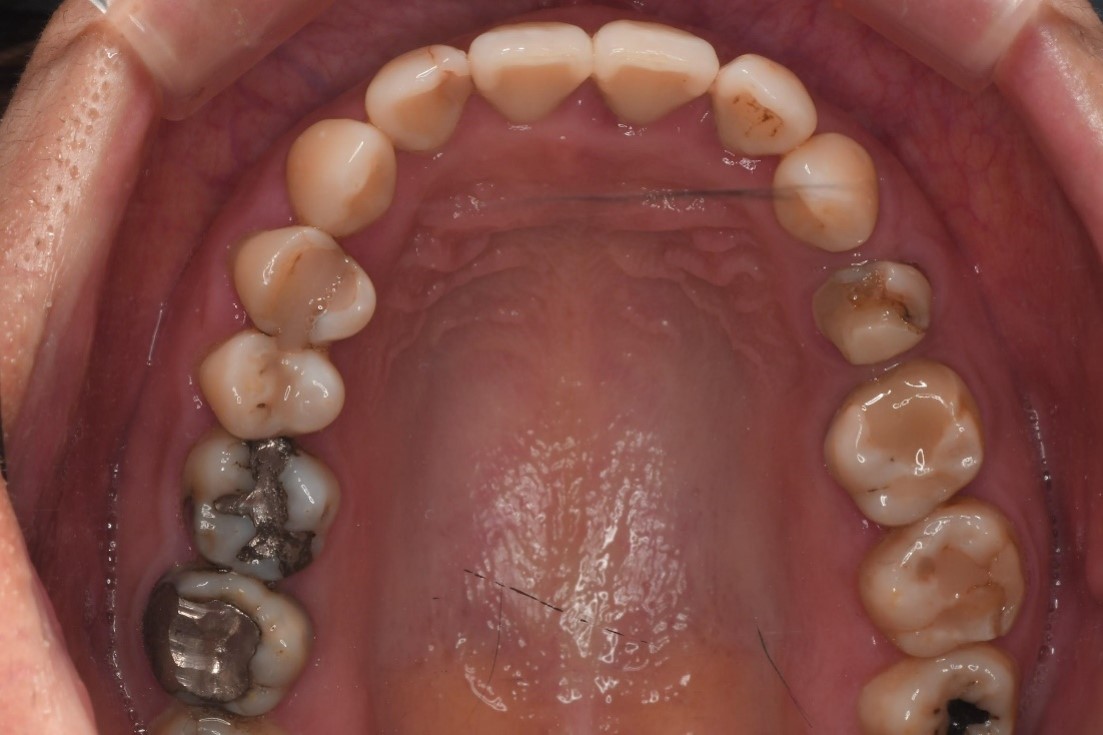

治療前,右上第二小臼齒疼痛

膺復前評估牙齦、牙齒狀態